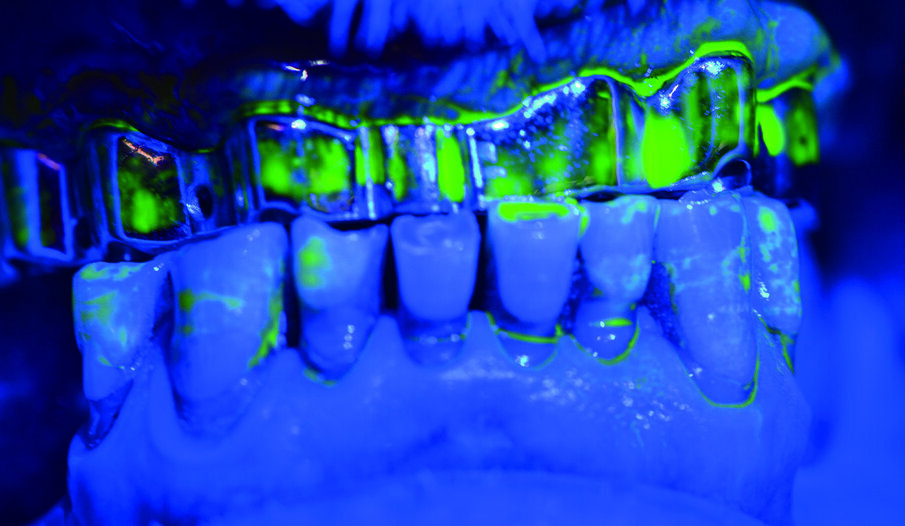

Documentiamo fotograficamente il cavo orale. Abbiamo mostrato al paziente, in real time, al fine di motivarlo a un più efficace controllo di placca domiciliare, i siti maggiormente interessati dall’accumulo di placca nel cavo orale, compresi, il dorso della lingua e gli spazi interprossimali e la barra implantare con l’aiuto del rilevatore di placca alla fluorescina Plac-o-Tect (Directa) (Fig. 10). Scegliamo per il paziente l’utilizzo corretto degli strumenti di igiene orale domiciliare – spazzolino e scovolino – più idonei alle sue esigenze strutturali, tissutali e anatomiche, alla manualità e alla predisposizione caratteriale alle differenti tecnologie manuali o meccaniche, come da tailored brushing method (Nardi et al., J Biomed, 2016).

Viene eseguito il deplaquing con approccio clinico D-Biotech (Dental Biofilm Detection Topographic Technique). L’operatore, dopo aver passato sulle superfici del cavo orale la spugnetta già intrisa di rivelatore di placca alla fluorescina Plac-o-Tect (Directa) osserva la topografia del biofilm batterico presente condividendola visivamente con il paziente in modo da avere un rinforzo motivazionale anche durante la seduta di igiene orale professionale. Questo approccio clinico permette di eseguire un lavoro efficace e minimamente invasivo, poiché consente all’operatore di strumentare con polishing selettivo, airpolishing o debridment con gli ablatori, esclusivamente seguendo la topografia del biofilm batterico con meno dispersione di glicina ed un timing ridotto dell’operatività (Fig. 13).